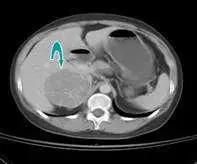

本題為反向題(問「最不可能」)的延伸題,接續上題情境:30歲女性出現聲音變粗、陰蒂增大等男性化(virilization)表現,電腦斷層(CT)顯示腎上腺區域病灶,血液檢驗 Testosterone 為 250 ng/dL、DHEAS(dehydroepiandrosterone sulfate,脫氫異雄固酮硫酸鹽)為 800 µg/dL。本題要求根據影像與賀爾蒙數值判斷最可能的診斷。

影像分析:

電腦斷層兩張橫切面影像均可見腎上腺區域(右側腎上腺附近)有以青色箭頭標示的軟組織密度腫塊,與正常腎上腺形態不符,提示為腎上腺佔位性病灶(adrenal mass)。

- 第一張影像:顯示上腹部橫切面,可見右腎上腺區域有界限清楚之腫塊,周圍結構受壓但無明顯鄰近器官侵犯表現。

- 第二張影像:另一層面顯示同一腫塊延伸範圍,腫塊為均勻密度,邊界尚清,影像特徵符合腎上腺功能性腺瘤(adrenal functional adenoma)或腎上腺皮質癌(adrenal cortical carcinoma)。

影像加上賀爾蒙數值(DHEAS 顯著升高至 800 µg/dL),共同指向腎上腺來源之高雄激素血症。